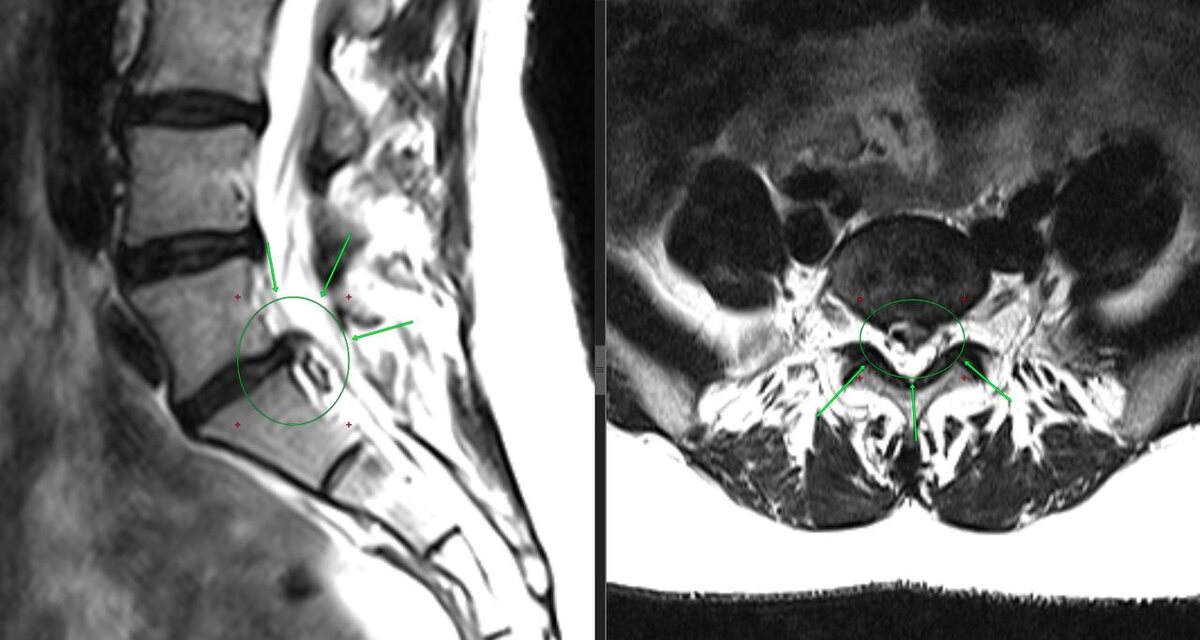

И тесты мне сказали то, что я уже понял из рассказа: классика жанра – разрыв межпозвонкового диска с грыжей. Наклон + прострел + боль в ягодицу = L5-S1 просит о помощи.

Направил на МРТ.

И да – грыжа диска L5-S1. Всё сходится.

Приходит на контрольный приём. Со свежим МРТ в руках.

Открываю снимок.

Грыжи нет.

Читаю ещё раз.